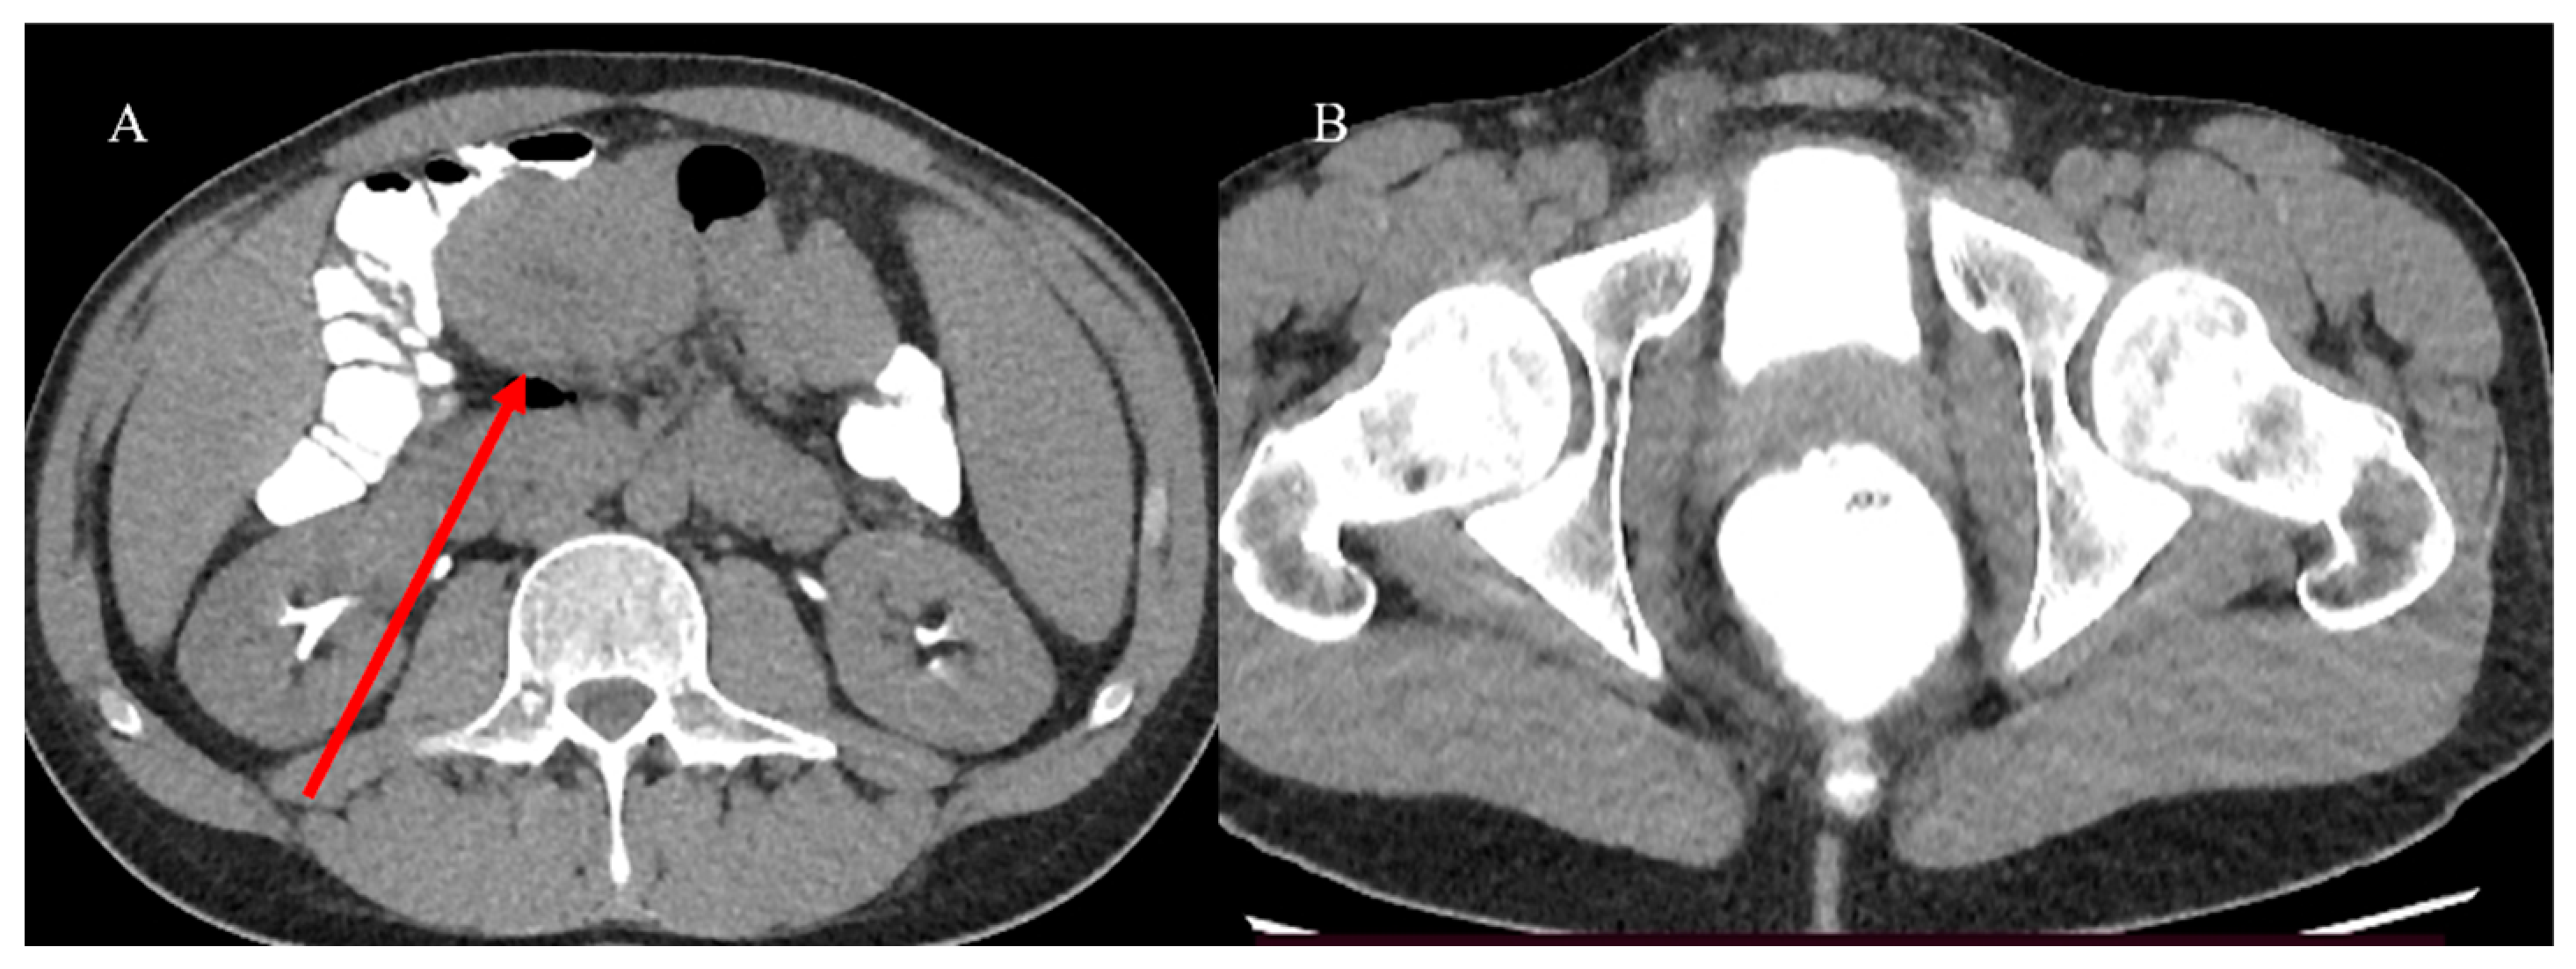

- Kim, Y.H.; Blake, M.A.; Harisinghani, M.G.; Archer-Arroyo, K.; Hahn, P.F.; Pitman, M.B.; Mueller, P.R. Adult intestinal intussusception: CT appearances and identification of a causative lead point. Radiographics 2006, 26, 733–744. [Google Scholar] [CrossRef]

- Choi, S.H.; Han, J.K.; Kim, S.H.; Lee, J.M.; Lee, K.H. Intussusception in adults: From stomach to rectum. AJR Am. J. Roentgenol. 2004, 183, 691–698. [Google Scholar] [CrossRef]

- Panzera, F.; Di Venere, B.; Rizzi, M.; Biscaglia, A.; Praticò, C.A.; Nasti, G.; Mardighian, A.; Nunes, T.F.; Inchingolo, R. Bowel intussusception in adult: Prevalence, diagnostic tools and therapy. World J. Methodol. 2021, 11, 81. [Google Scholar] [CrossRef] [PubMed]